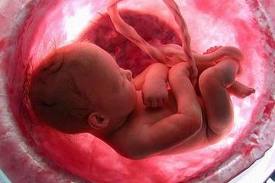

Il pancione è cresciuto ancora e non permette di vedere neanche i piedi. Il bambino pesa circa 2 kg ed è lungo circa 38 cm. Ogni settimana metterà su tra i 200 e i 250 gr e diventerà sempre più cicciottello. Le ossa cominciano a solidificarsi, esclusa la scatola cranica, che deve rimanere malleabile per permettere la nascita.

Il piccolo continua a crescere e dovrebbe pesare circa 2250 grammi, ma le stime del peso fetale sono variabili e oscillano di circa il 10% in più o in meno a quanto segnalato. Infatti, ora ci si basa su dei calcoli di equazioni matematiche partendo dalle misure ecografiche della circonferenza cranica, della circonferenza addominale e della lunghezza del femore che possono orientare sul peso, ma non darne la certezza.

Ora il bambino ha assunto la posizione cefalica, ossia la posizione a testa in giù, ed è possibile avvertire dei fastidi sul collo dell’utero e sulle ossa pubiche. In realtà, sotto l’effetto della relaxina, i legamenti delle articolazioni fisse si ammorbidiscono, per facilitare il passaggio del bambino durante la nascita.

Il peso del piccolo è arrivato intorno ai 2550 gr., è più rotondo, si muove in rapporto al poco spazio che ha a disposizione e il suo sistema neurologico è ben sviluppato.

Il bambino è arrivato a pesare circa 2750 grammi ed è lungo circa 48 centimetri. Il suo corpicino comincia a perdere la peluria e la vernice caseosa che l’ha ricoperto finora per proteggerlo dall’azione irritante del liquido amniotico. Queste e altre sostanze sono ingerite dal piccolo con il liquido e vanno a formare il meconio.